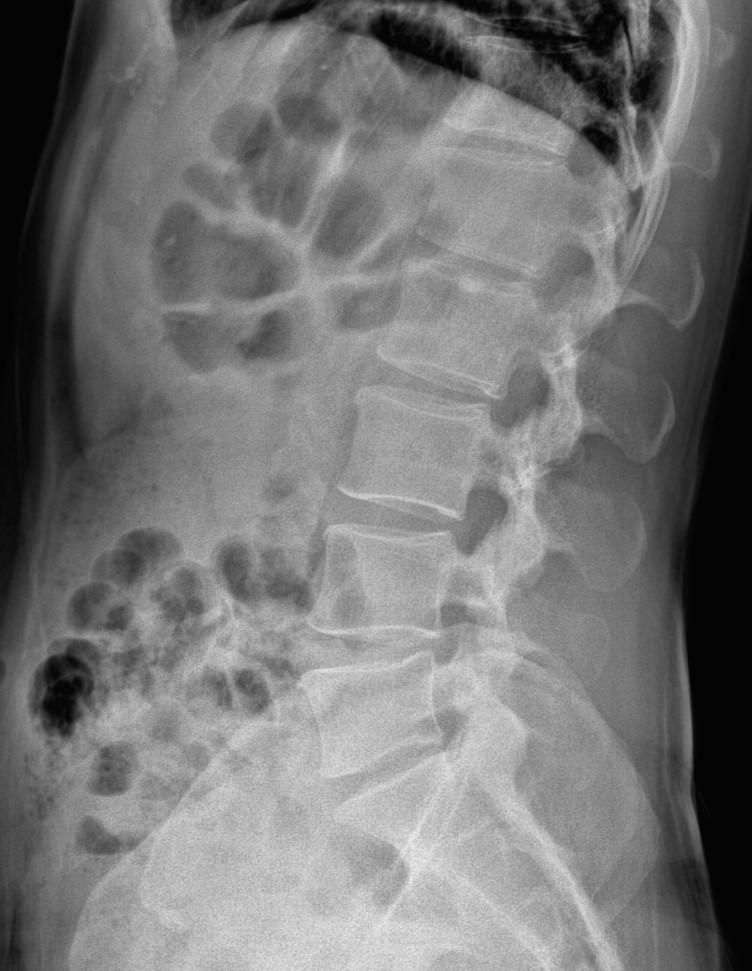

허리랑 고관절 엑스레이사진판독 조언 부탁드립니다

간헐적인 약간의 찌릿 뜨끔 한 오른쪽허리통증이 근한달정도

허리를 굽힌다던지등의 특정자세에 오는것 같진 않습니다

최근 한몇일은 일시적 뻐근한 느낌도 있고요

엑스레이 상에서는 요추 배열이 전반적으로 잘 유지돼 보입니다. 마나 일부 요추 간격이 좁아진 부위가 있어 보입니다. 말씀하신 것처럼 특정 동작에서 찌릿 혹은 뜨끔하거나, 최근 뻐근함이 생기는 건 디스크 초기나 근육, 인대 긴장에서도 나타날 수 있습니다.

허리의 커브가 줄어들어있다는것을 제외하고는 크게 문제가될만한 부분은없는데요 통증과불편감이 지속된다면 MRI와같은 정밀검사가 필요할수있습니다

사진상 요추 사이의 간격이 다소 좁아 보이며 간격이 좁다는 것은 퇴행성 변화를 의미하며 척추의 정렬 또한 큰 전위는 없어 보이나 허리 곡선이 정상보다는 조금 감소한 상태로 이러한 경우 근육의 긴장이나 만성적인 통증이 발생할 수 있습니다.

• 엑스레이 검사를 통해서는 현실적으로 뼈 위주의 평가만 가능하며 정밀하고 자세하게 평가를 내리는 것은 어렵습니다. 올리신 엑스레이 사진들에는 특별히 문제가 있다고 볼만한 소견이 크게 있어보이거나 하지는 않습니다.

우선 현재로썬 척추와 척추 사이인 디스크 공간이 좁지는 않아보이지만 다소 요추의 커브가 감소되어 있어 보입니다.